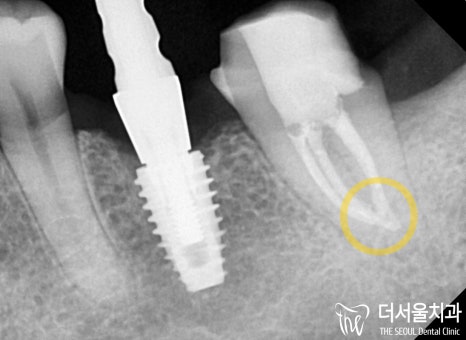

『누운 사랑니 발치 후, 우식 제거』

일단 문제가 되었던 누운 사랑니 부터

깔끔하게 뽑아주기로 하였습니다.

누운 사랑니 를 발치할 때에는

신경관이나 인접치들을 고려해야 된다는 거 알고 계시죠?

무엇보다 중요한 최. 소. 절. 개.로 진행했답니다.

이후 본격적으로 근관치료 과정을 진행했습니다.